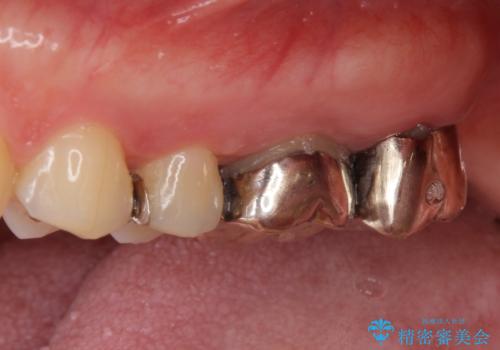

- 銀歯をやりかえたいが他院で抜歯と言われセカンドオピニオンで来院。適合の悪い被せ物が入っており、まずは古い材料、虫歯をとり保存可能か確かめる必要があり、拡大鏡下で全て取り除いたら歯質が歯茎の中まで虫歯がありました。このまま無理やり型取りをして被せ物を作っても不適合な被せ物が入る可能性が高いため歯茎を切り取る手術(ディスタルウェッジ)を行いました。そして再根管治療を行いゴールドの被せ物で治療を行いました。

- PGAクラウン・仮歯 13.2万円×2 精密根管治療(リトリートメント)・コア 16.5万円×2 ディスタルウェッジ 1万円費用は治療当時の料金となります

適合の良い被せ物が入り大変満足して頂けました。